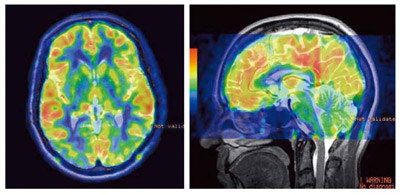

図6 3D ASL(CBFカラーマッピング)

CubeによるT2強調のボリューム撮像との重ね合わせ。

3D ASLはリードアウトをFSEとしているため,比較的容易に他の画像とのフュージョンが可能である。